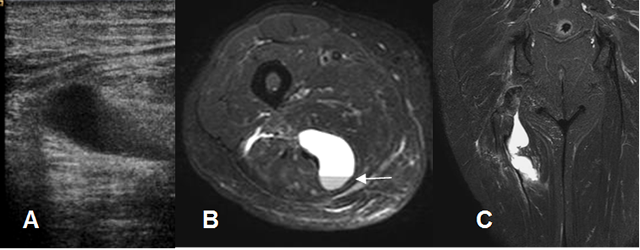

Fig 22. Ruptura muscular.

A: Ecografía. Colección líquida en la región posterior del muslo.

B: RM axial y C: RM coronal en STIR. Hematoma intermuscular con nivel líquido/líquido entre los músculos, por ruptura en el origen de los isquiotibiales.